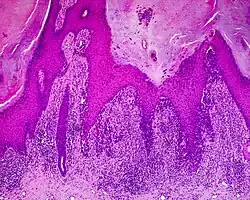

Histology

The main characteristic of acral lentiginous melanoma is continuous proliferation of atypical melanocytes at the dermoepidermal junction.[15] Other histological signs of acral lentiginous melanoma include dermal invasion and desmoplasia.[16]

According to Scolyer et al.,[17] ALM "is usually characterized in its earliest recognisable form as single atypical melanocytes scattered along the junctional epidermal layer".

Acral lentiginous melanoma (ALM)

Acral lentiginous melanoma (ALM)